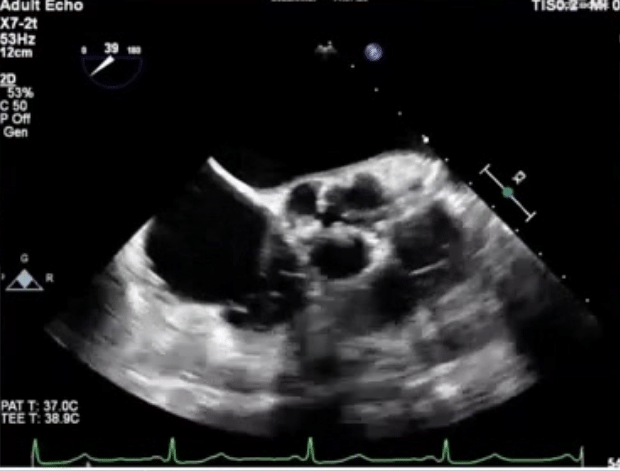

入院检查心电图窦性心律,未见明显异常。超声心动图资料如下所示:

超声提示:

主动脉瓣钙化,致主动脉瓣重度狭窄伴轻度反流(考虑老年钙化性主动脉瓣病)

左心增大

二尖瓣后叶瓣环钙化斑伴轻度反流

三尖瓣轻度反流

左室舒张功能减低,收缩功能正常

充分术前准备后,患者术中食道超声心动图可见三叶瓣主动脉瓣膜狭窄,明显钙化,主动脉瓣中度中心性返流。超声实测瓣环前后经20mm,左右径26mm,窦部内径33mm,窦管交界25mm,右冠开口高度16mm,左冠开口高度15mm,瓣叶长度13mm左右。患者心功能良好,EF(射血分数)值69%。